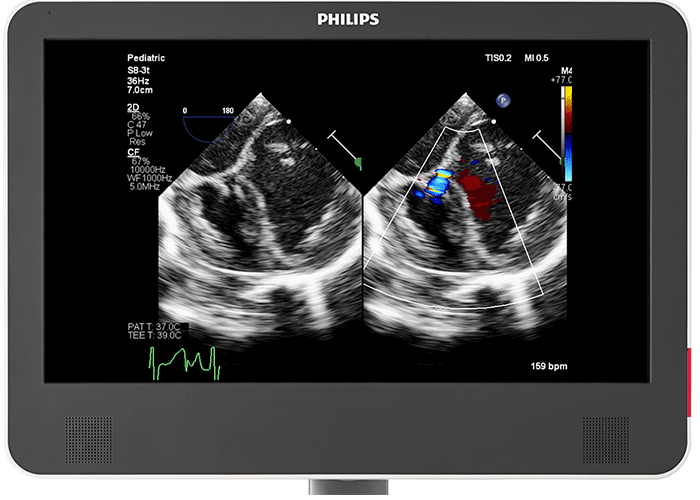

A screen built to be seen The 22-inch, 2nd generation OLED monitor on the Philips EPIQ CVx gives you an image 38% larger than traditional ultrasound images with no loss of resolution. As well as a 180° viewing angle, it also delivers a greater dynamic range, and a wider colour range over its predecessor. This enhances your view of side-by-side, colour compare, and all images.

Designed for next-generation Live 3D TEE The acoustic design of the Philips X8-2t Live 3D transesophageal transducer provides higher frequencies and bandwidth for increased resolution and tissue filling in 2D and Live 3D. It brings true one-beat acquisitions and our highest volume rates in Live 3D and Live 3D colour flow without compromise to image quality. Its handle is designed with a real-time configurable function button allowing for additional functionality while imaging.

The Philips EPIQ CVx builds on a long tradition of innovative firsts in paediatric cardiology with the addition of many dedicated paediatric cardiology innovations like the Philips S9-2 transducer - a dedicated paediatric PureWave 2D TTE transducer - as well as a one-button coronary sub-mode, and an innovative 3D photo-realistic image rendering. The EPIQ CVx boasts a wide range of 2D and 3D transthoracic and transesophageal transducers for use from foetal to neonates to paediatrics to an adult congenital patient population.

A screen built to be seen The 22-inch, 2nd generation OLED monitor on the Philips EPIQ CVx gives you an image 38% larger than traditional ultrasound images with no loss of resolution. As well as a 180° viewing angle, it also delivers a greater dynamic range, and a wider colour range over its predecessor. This enhances your view of side-by-side, colour compare, xPlane, Live 3D, MPRs and stress echo images.